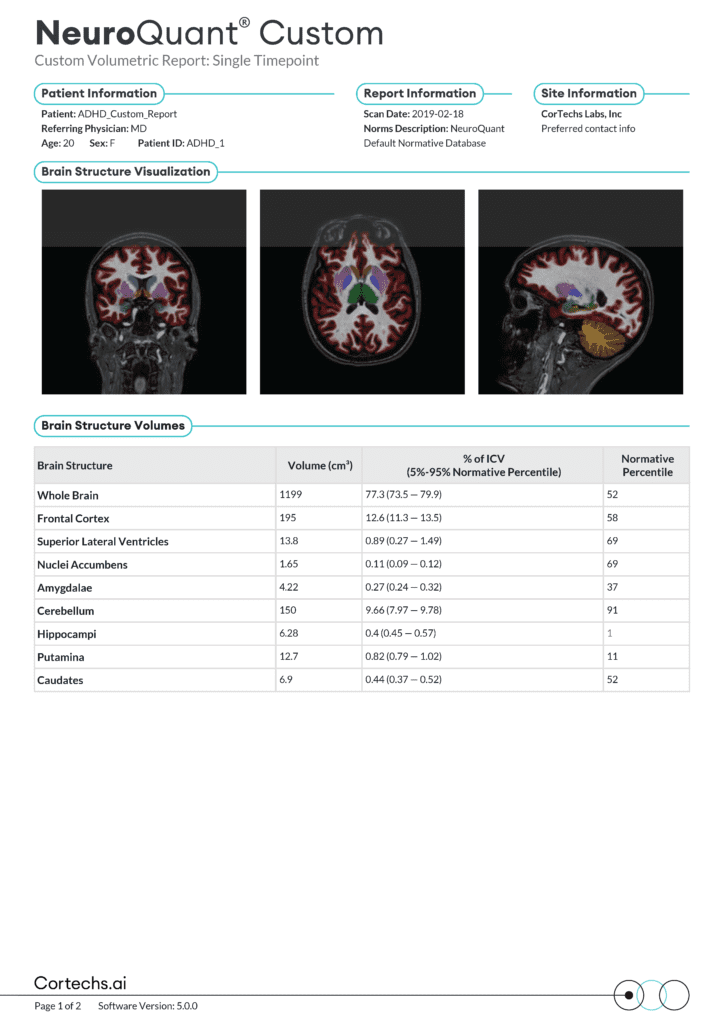

Automated brain segmentation and volumetric analysis designed to support assessment of neurodegenerative and neurological conditions. Compares patient-specific brain volumes against age- and sex-matched normative databases.

- Objective assessment of brain structure volumes

- Early identification of neurodegeneration patterns

- Longitudinal tracking of disease progression

- Improved consistency and inter-reader agreement